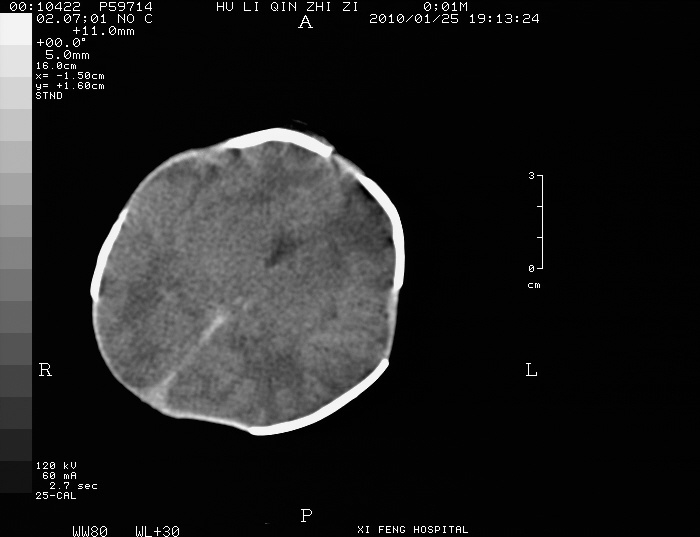

男  新生儿,曾做b超股骨长5.5厘米,疑畸形,家族中有多个身才矮小.曾孕两次,一次流产,一次宫内死亡

常染色体上显性致病基因a引发的一种显性遗传病,表现四肢短小畸形,上臂和大腿表现得尤为明显,骨骺软骨发育不全呈点状;腹部明显隆起,患者身材短小,智力正常。

四肢干骺端呈喇叭口型缺损,颅骨缝增宽,支持软骨发育不全。